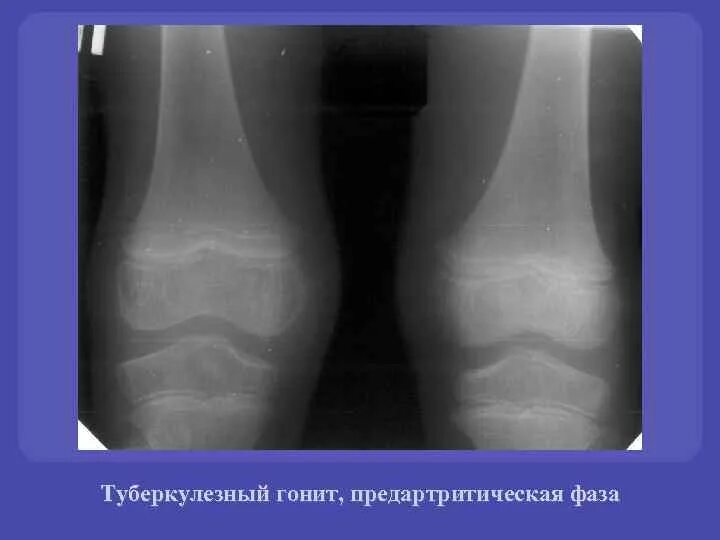

Гонит это